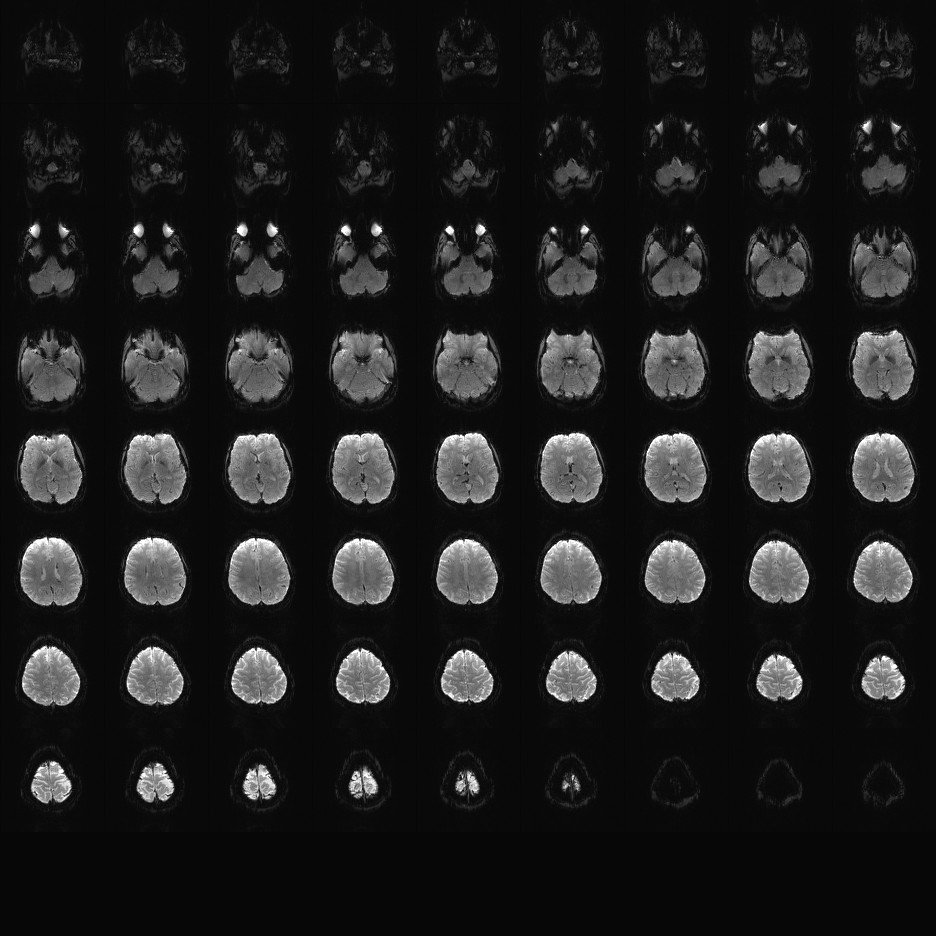

Multi-banded RF pulses can be used to accelerate volume coverage along the slice direction by simultaneously exciting and acquiring multiple slices and subsequently unaliasing them using parallel imaging principles and the spatial information available in multi-channel RF array coils.

This allows for a direct reduction in the volume TR by the number of simultaneously excited slices (i.e., the multiband (MB) factor or the slice acceleration factor).